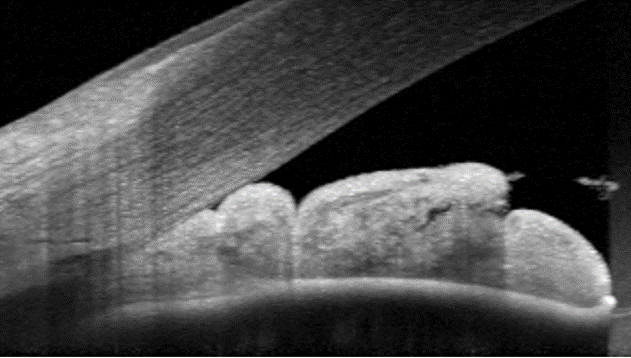

Anterior OCT (right eye)

More infoAnterior OCT (left eye)